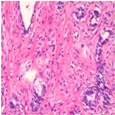

| Image Class | BreakHis Dataset(40×) | |||

| Benign | Malignant | |||

| Original images |  |  |  |  |

| MFF-ClassificationNet heatmaps |  |  |  |  |